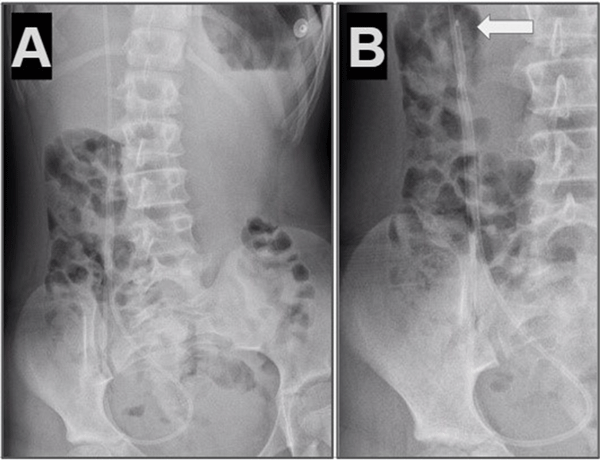

Caso 3. Paciente femenina de 7 años con antecedentes de síndrome de Moebius, hidrocefalia congénita y colocación de DVP al nacer que presentó vómitos e irritabilidad. Tomografía de cerebro simple evidenció dilatación ventricular en comparación con imágenes previas. Radiografía de sistema mostró catéter distal fuera de la cavidad peritoneal (Figura 3).

Figura 3. Caso 3: A) Se observa Rx de tórax y abdomen (frente) con catéter distal a nivel abdominal con migración retrógrada. B) Magnificación de Rx de abdomen que evidenció catéter en doble caño con signo radiológico del “caño de escopeta” o “signo del anzuelo” (flecha blanca) C) Imagen intraoperatoria que muestra la regresión del catéter en disposición paralela con la imagen típica de “doble caño” o “caño de escopeta”.

Caso 4. Paciente femenina de 10 años con antecedentes de nacimiento prematuro, hidrocefalia congénita y colocación DVP al mes de vida. Consultó por cuadro de cefalea y vómitos, tomografía de cerebro simple evidenció mayor tamaño ventricular en comparación con estudios previos. Radiografía de sistema mostró catéter distal fuera de la cavidad peritoneal (Figura 4).

Figura 4. Caso 4: A) Se observa Rx de tórax y abdomen (frente) con catéter distal a nivel abdominal con migración retrógrada. B) Magnificación de Rx de abdomen que evidencia catéter en doble caño con signo radiológico del “caño de escopeta” o “signo del anzuelo” (flecha blanca).